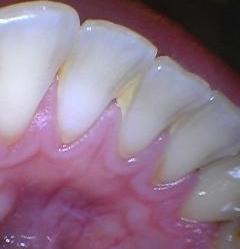

Does your gum bleed easily every time you brush your teeth?